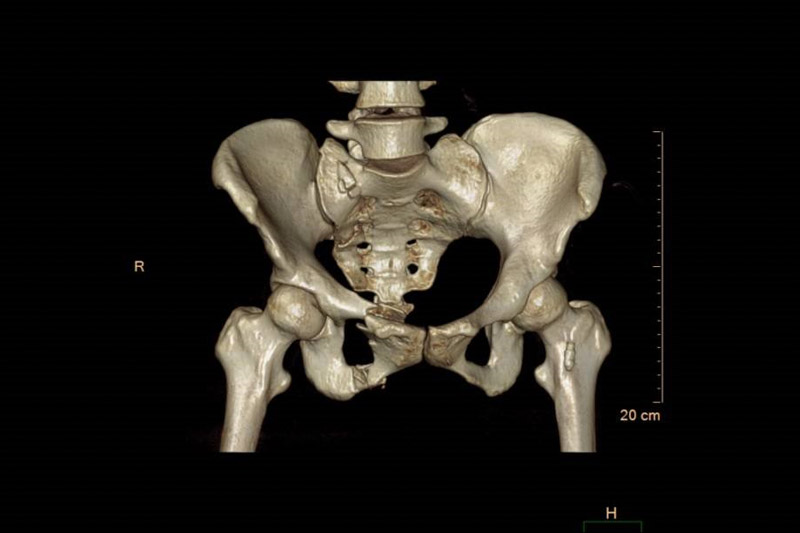

患者周女士在走路時不慎被車撞傷,被120送至當地醫院,清醒后感覺臀部劇痛難忍,雙髖活動受限,為求進一步治療,轉入了柳州市人民醫院創傷骨科,經CT檢查,患者為骨盆骨折,需手術治療。

骨盆位置深,內部臟器結構豐富,血管神經復雜,一旦發生損傷,常常導致相應的血管神經損傷和大出血,所以骨盆骨折手術一直被認為是創傷骨科中最復雜的手術之一。且傳統切開復位內固定手術對患者傷害較大,容易造成術中血管神經的損傷、術后感染等并發癥的發生。

創傷骨科專家團隊經過周密的術前討論,決定術中采用智能可視化機器人作為“新助手”,輔助精準定位,為患者行骨盆骨折經皮微創內固定術。不同于表面軟組織,經皮微創骨科手術無法直視,更像是在堅硬的暗箱內操作。骨科手術機器人突破了傳統手術中“手”“眼”的局限,術前對患處進行影像掃描并進行詳細規劃,手術中醫生可以通過機器人的“透視眼”,將虛擬手術計劃轉變為現實空間位置,手術路徑更加精確,穿刺針的長度、寬度和進入骨骼的角度更加準確。